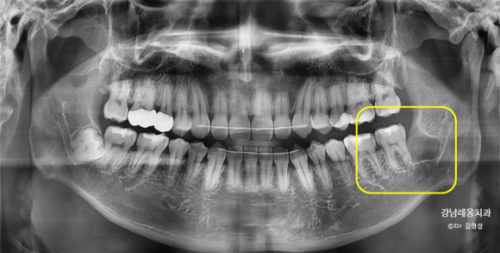

다행히 뿌리를 모두 잘 발치하였고

발치 후 엑스레이 촬영을 통해

남은 조각이 또 있지 않은지 확인하였습니다.

정확한 계획대로 발치를 진행했으나

추후 신경손상 증상이 없는지

일주일 동안 체크를 할 필요가 있습니다.

일주일 후 회복이 잘 되었고

신경손상없이 모두 정상이었습니다.